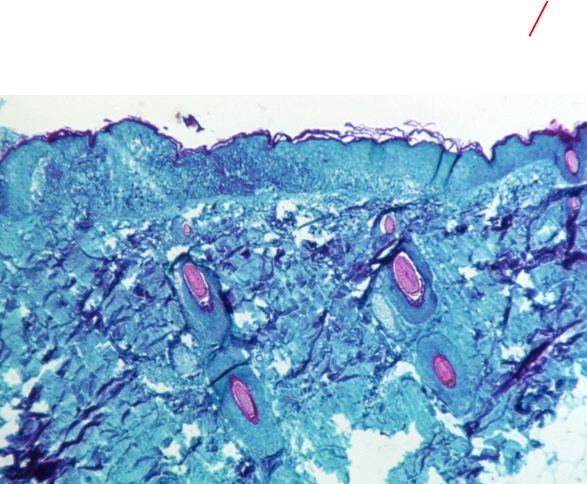

وتظهر أعراض المرض على هيئة حمى وتضخم في الغدد الليمفاوية وآلام في العضلات والتهاب حلق، إضافة إلى الإرهاق والقشعريرة وطفح جلدي يشبه جدري الماء على اليدين والوجه وباطن القدمين والأعضاء التناسلية وغيرها من أجزاء الجسم.

واكتشف جدري القرود أول مرة عام 1958، عندما ظهر مرض يشبه الجدري في قرود أحد المختبرات، ومن هنا أُخذت هذه التسمية.